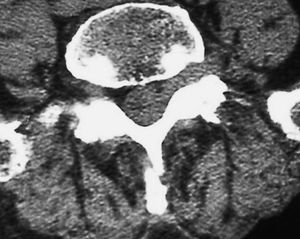

Fig. 2--TC sin contraste. Corte axial. Lesión en margen lateral del canal, foramina y espacio extraforaminal, con pequeña burbuja de gas en su interior. No se aprecian erosiones óseas.

Varón de 77 años con lumbociatalgia izquierda de tres meses de evolución. Se practica tomografía computarizada (TC) y resonancia magnética (RM) de columna lumbar.